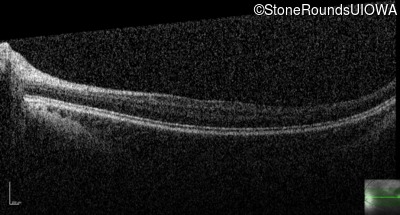

Optical Coherence Tomography - Left - 20/63 -2

Exemplar / OCT Stack

OCT Stack